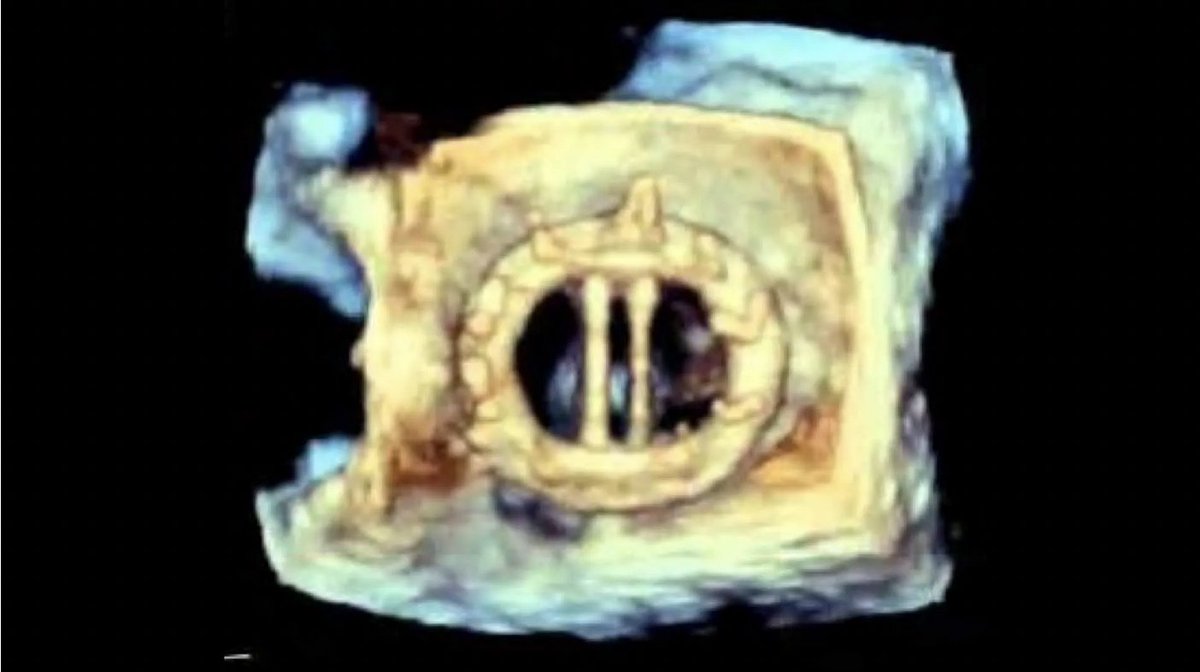

Importancia pronóstica del acoplamiento ventriculoarterial derecho en pacientes sometidos a cirugía aislada de la válvula tricúspide #REC Manuel Carnero Julian P Villacastin Alberto de Agustin Eduardo Pozo revespcardiol.org/es-importancia…

Prognostic significance of right ventriculoarterial coupling in patients undergoing isolated tricuspid valve surgery #REC Manuel Carnero Julian P Villacastin Alberto de Agustin Eduardo Pozo revespcardiol.org/en-prognostic-…